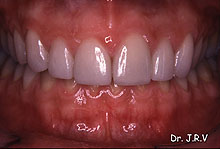

| Fotos

4E, 4F, 4G y 4H.- Dientes 12 y 22 conoides antes y después de su tratamiento

con dos carillas de porcelana. Se colocaron también carillas en los dos

incisivos centrales. |

| Foto 4I.- Sonrisa antes del tratamiento. |

Foto 4J.- Sonrisa después de cementar las cuatro carillas de porcelana. |